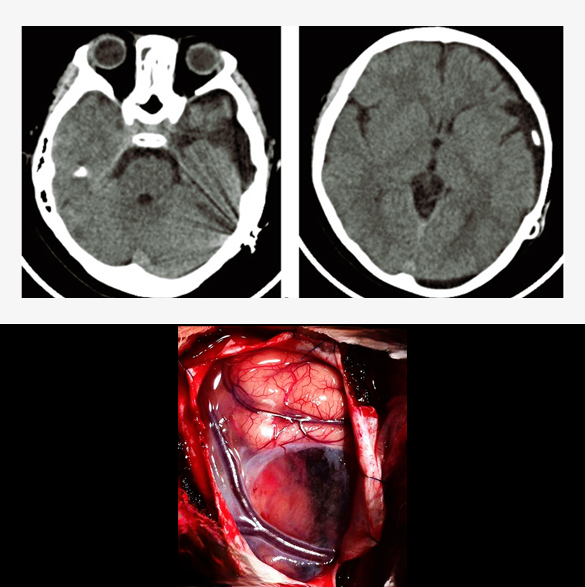

Head Trauma Surgery

Surgery in case of a head trauma is performed when there is intracranial hematoma (blood) of significant amount or depressed skull fracture causing pressure on the normal brain. This life-threatening condition necessitates emergency surgery in a well-equipped environment, often requiring postoperative intensive care unit (ICU) admission. Surgery, called craniotomy, is performed to open up the skull and remove the hematoma or reposition the depressed skull bone. Sometimes, a part of skull bone is removed (called decompressive craniectomy) to control the intracranial pressure, requiring a second surgery to replace the bone, months later after complete recovery. Complications of the surgery can be rebleeding, infection, hydrocephalus, seizures, paralysis, coma or even death in severe case.